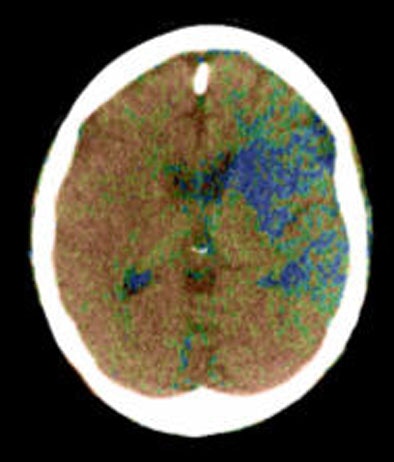

| Top to bottom: Perfusion CT images overlaid on CT source images of a 73-year-old male patient. The patient was scanned 30 minutes after the sudden onset of right hemiparesis with an NIHSS of 20. Above, cerebral blood flow (CBF) map shows a blue-color area of low CBF (range: 0-12 mL/100g/min) in the basal ganglia on the left side, which corresponds to the irreversibly infarcted tissue. Note the peripheral area displayed as green, which corresponds to the penumbra region (range: 12-24 mL/100 g/min). In the image below, cerebral blood volume (CBV) map does not demonstrate a clear delineation of the infarcted region in comparison with the CBF map. In the bottom image, mean transit time (MTT) map shows a slightly larger abnormality than seen on the CBF map. Images courtesy of Dr. Sotirios Bisdas. |